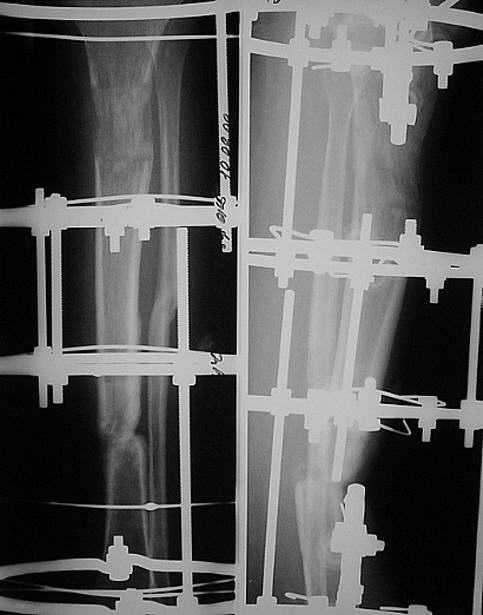

сделан первый этап операции: остеосинтез спице-стержневым аппаратом 7.11.09 г. выполнен второй этап - БИОС с рассверливанием канала, операция прошла без ожидаемых трудностей, открывать зону ложного сустава не пришлось. Прошу сделать замечания.

Виктор Попов, Караганда.

Рекурвация вроде осталась. Недорепонировали на этапе ЧКО.

И точка входа слишком низко.

И гвоздик коротковат imho.

Мы бы сделали заход через переднее межмыщелковое поле, тогда бы динамический блокирующий винт в овальном отверстии прошёл бы через нормальную кость, а не через регенерат. Ну, и стержень, соответственно, потребовался бы длиннее.

Уважаемый коллега! Однозначно надо было произвести первичную динамизацию!!! Мне кажется в целом не плохо сделано, если пациент еще в стационаре не поздно убрать статические винты. Иначе остеотомированный м/б кость ч/з 3 нед срастется и будеть распоркой. С уважением Ерсин Жунусов.

"Рекурвация вроде осталась. Недорепонировали на этапе ЧКО. точка входа слишком низко динамическое блокировани, гвоздик коротковат imho

Небольшие технические погрешности вряд ли кардинально повлияют на окончательный результат. Я бы поздравил уважаемого Виктора с успешным решением трудной задачи с использованием новой технологии и, самое главное, больную с реальным появлением надежды на выздоровление после длительного периода применения предшествующей конструкции с сомнительным прогнозом на исход.

Уважаемые коллеги Djoldas, Ерсин, Danil. Спасибо за обсуждение случая, за конструктивные замечания, которые помогут при выполнении следующей операции. Глубокоуважаемый Djoldas огромное спасибо за поддержку.